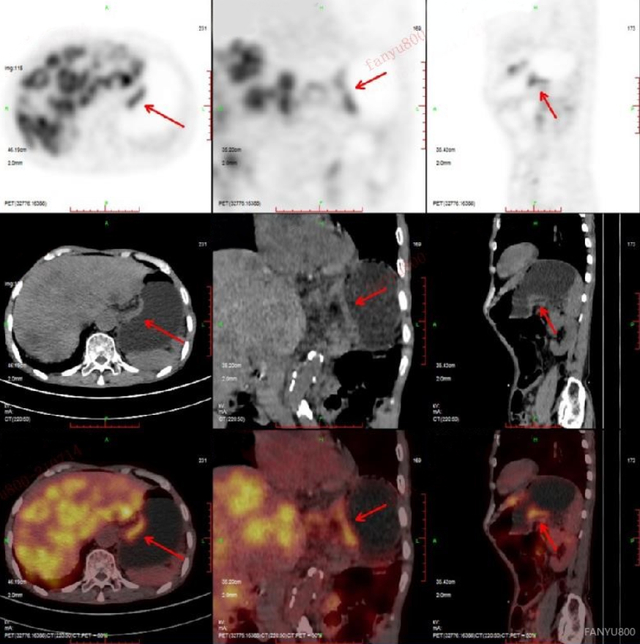

病例3

可疑肝转移患者PET/CT发现原发灶

男性,78岁

相关病史:一直觉得腹部疼痛,在基层医院CT检查,发现肝脏多发低密度灶,怀疑为肝脏多发转移。之后患者在平安健康(检测)中心接受PET/CT检查。

PET/CT影像学表现

上图为肝脏的横断位、冠状位及矢状位图像,依次为PET图像、CT图像、融合图像。图示肝脏体积稍增大,肝内弥漫分布大小不等类圆形低密度灶,部分相互融合,边界不清 ,相应部位放射性摄取明显增高,SUV最大值8.50。

上图显示横断位示胃充盈佳,胃体小弯侧增厚,相应部位放射性摄取异常增高,SUV最大值6.29。

上图中冠矢状位也清楚地显示胃体小弯侧的增厚及FDG代谢的增高。

PET/CT找出原发灶

最后PET/CT诊断为胃癌伴肝脏多发转移,给临床指明了方向,可以制定更针对性的治疗方案。